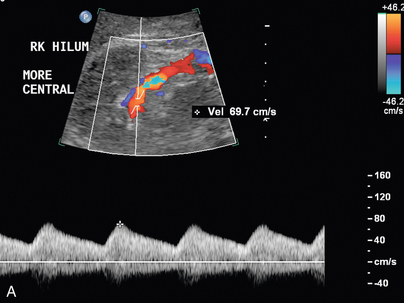

Артериовенозная фистула в нативной почке встречается редко, за исключением случаев предшествующей биопсии почки, и ее нельзя заподозрить при сонографии, если не проводится цветная или энергетическая допплерография. Цветной или энергетический допплер обычно показывает большое извилистое скопление сосудов. Спектральные допплеровские сигналы почечных артерий, питающих фистулу, покажут высокую скорость и низкое сопротивление ( рис. 9-19 ). Основная почечная вена может быть расширена, а в венах вблизи фистулы могут обнаруживаться артериализованные волны ( рис. 9-20 ).

РИСУНОК 9-20. Артериовенозная фистула. (А) Спектральная допплерография демонстрирует артериализованный венозный поток с высокими скоростями и низким сопротивлением. (B) КТ-ангиография показывает раннее усиление правой почечной вены (стрелка) по сравнению с левой почечной веной.